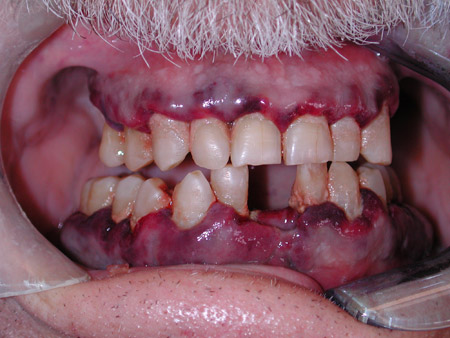

პერორალური პეტექიები ან სისხლჩაქცევები (თრომბოციტოპენია)

ღრძილების ჰიპერპლაზია (ლეიკემია)

[Figure caption and citation for the preceding image starts]: ღრძილების გადიდება, პეტექიები და სისხლდენა მწვავე მიელოიდური ლეიკემიის დროსCollection of Giuseppina Campisi, DDS, MS and Giuseppe Pizzo, DDS [Citation ends].